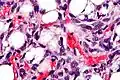

![Histopathology of liposarcoma, H&E stain, with the main features:[5] - Spindle cells with enlarged, hyperchromatic nuclei. - Apparently univacuolated adipocytes (may look normal). - Lipoblasts (multivacuolated), but neither necessary nor sufficient for diagnosis of liposarcoma.](./_assets_/Histopathology_of_liposarcoma%252C_annotated.jpg) Histopathology of liposarcoma, H&E stain, with the main features:[5]

Histopathology of liposarcoma, H&E stain, with the main features:[5]

- Spindle cells with enlarged, hyperchromatic nuclei.

- Apparently univacuolated adipocytes (may look normal).

- Lipoblasts (multivacuolated), but neither necessary nor sufficient for diagnosis of liposarcoma. -